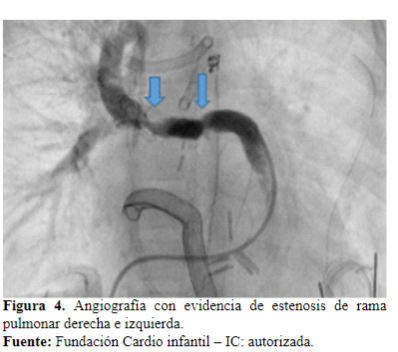

Dos días después es llevada a cateterismo cardíaco para ampliar estudios, donde se evidencia estenosis en la unión de la rama derecha con el conducto (Figura 4). Se realiza angioplastia con stent, queda con buena luz y buen flujo en el pulmón izquierdo (Figura 5y 6).